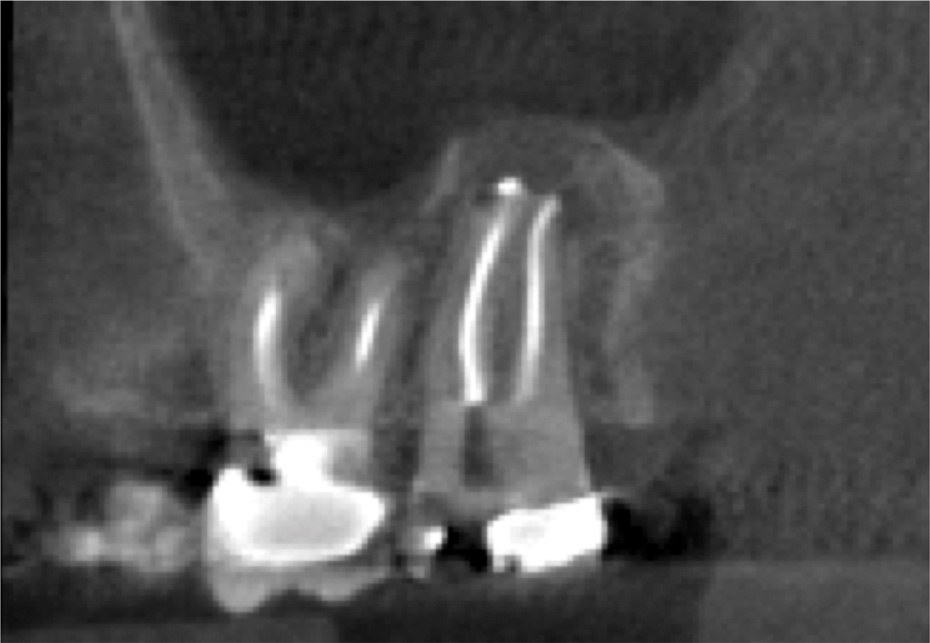

For patients suffering from MSEO, radiographs will reveal a periapical radiolucency with adjacent opacification in the maxillary sinus.12 Additional radiographic findings associated with MSEO include periapical mucositis and periapical osteoperiostitis (PAO). Periapical mucositis refers to mucosal thickening or dome-shaped soft-tissue expansion on the floor of the sinus directly adjacent to the infected root apex.PAO refers to the reactive osteogenesis caused by a local periosteal reaction that expands the sinus periosteum and displaces it upward into the sinus. It appears as a radiopaque "halo" surrounding the root apex (Figure 2 through Figure 4). PAO may be symptomatic and/or accompanied by adjacent mucosal edema and elevated sinus fluid levels.9 If left untreated, PAO can progress and result in a direct communication between the root apex and maxillary sinus.6,13 Unless bilateral odontogenic pathosis is found, the sinus opacifications will usually be unilateral and centered around the odontogenic source. Complete unilateral sinus opacifications may be missed on the CBCT images typically used in endodontics due to their limited or focused field of view (Figure 5). In cases involving complete unilateral sinus opacification, referral to an ENT or oral surgeon is essential to rule out invasive fungal infection or malignancy.2,17,24

(3.) Sagittal slice of CBCT image of the same tooth displaying PAO or “halo lesion” with associated mucositis.

Figure 3